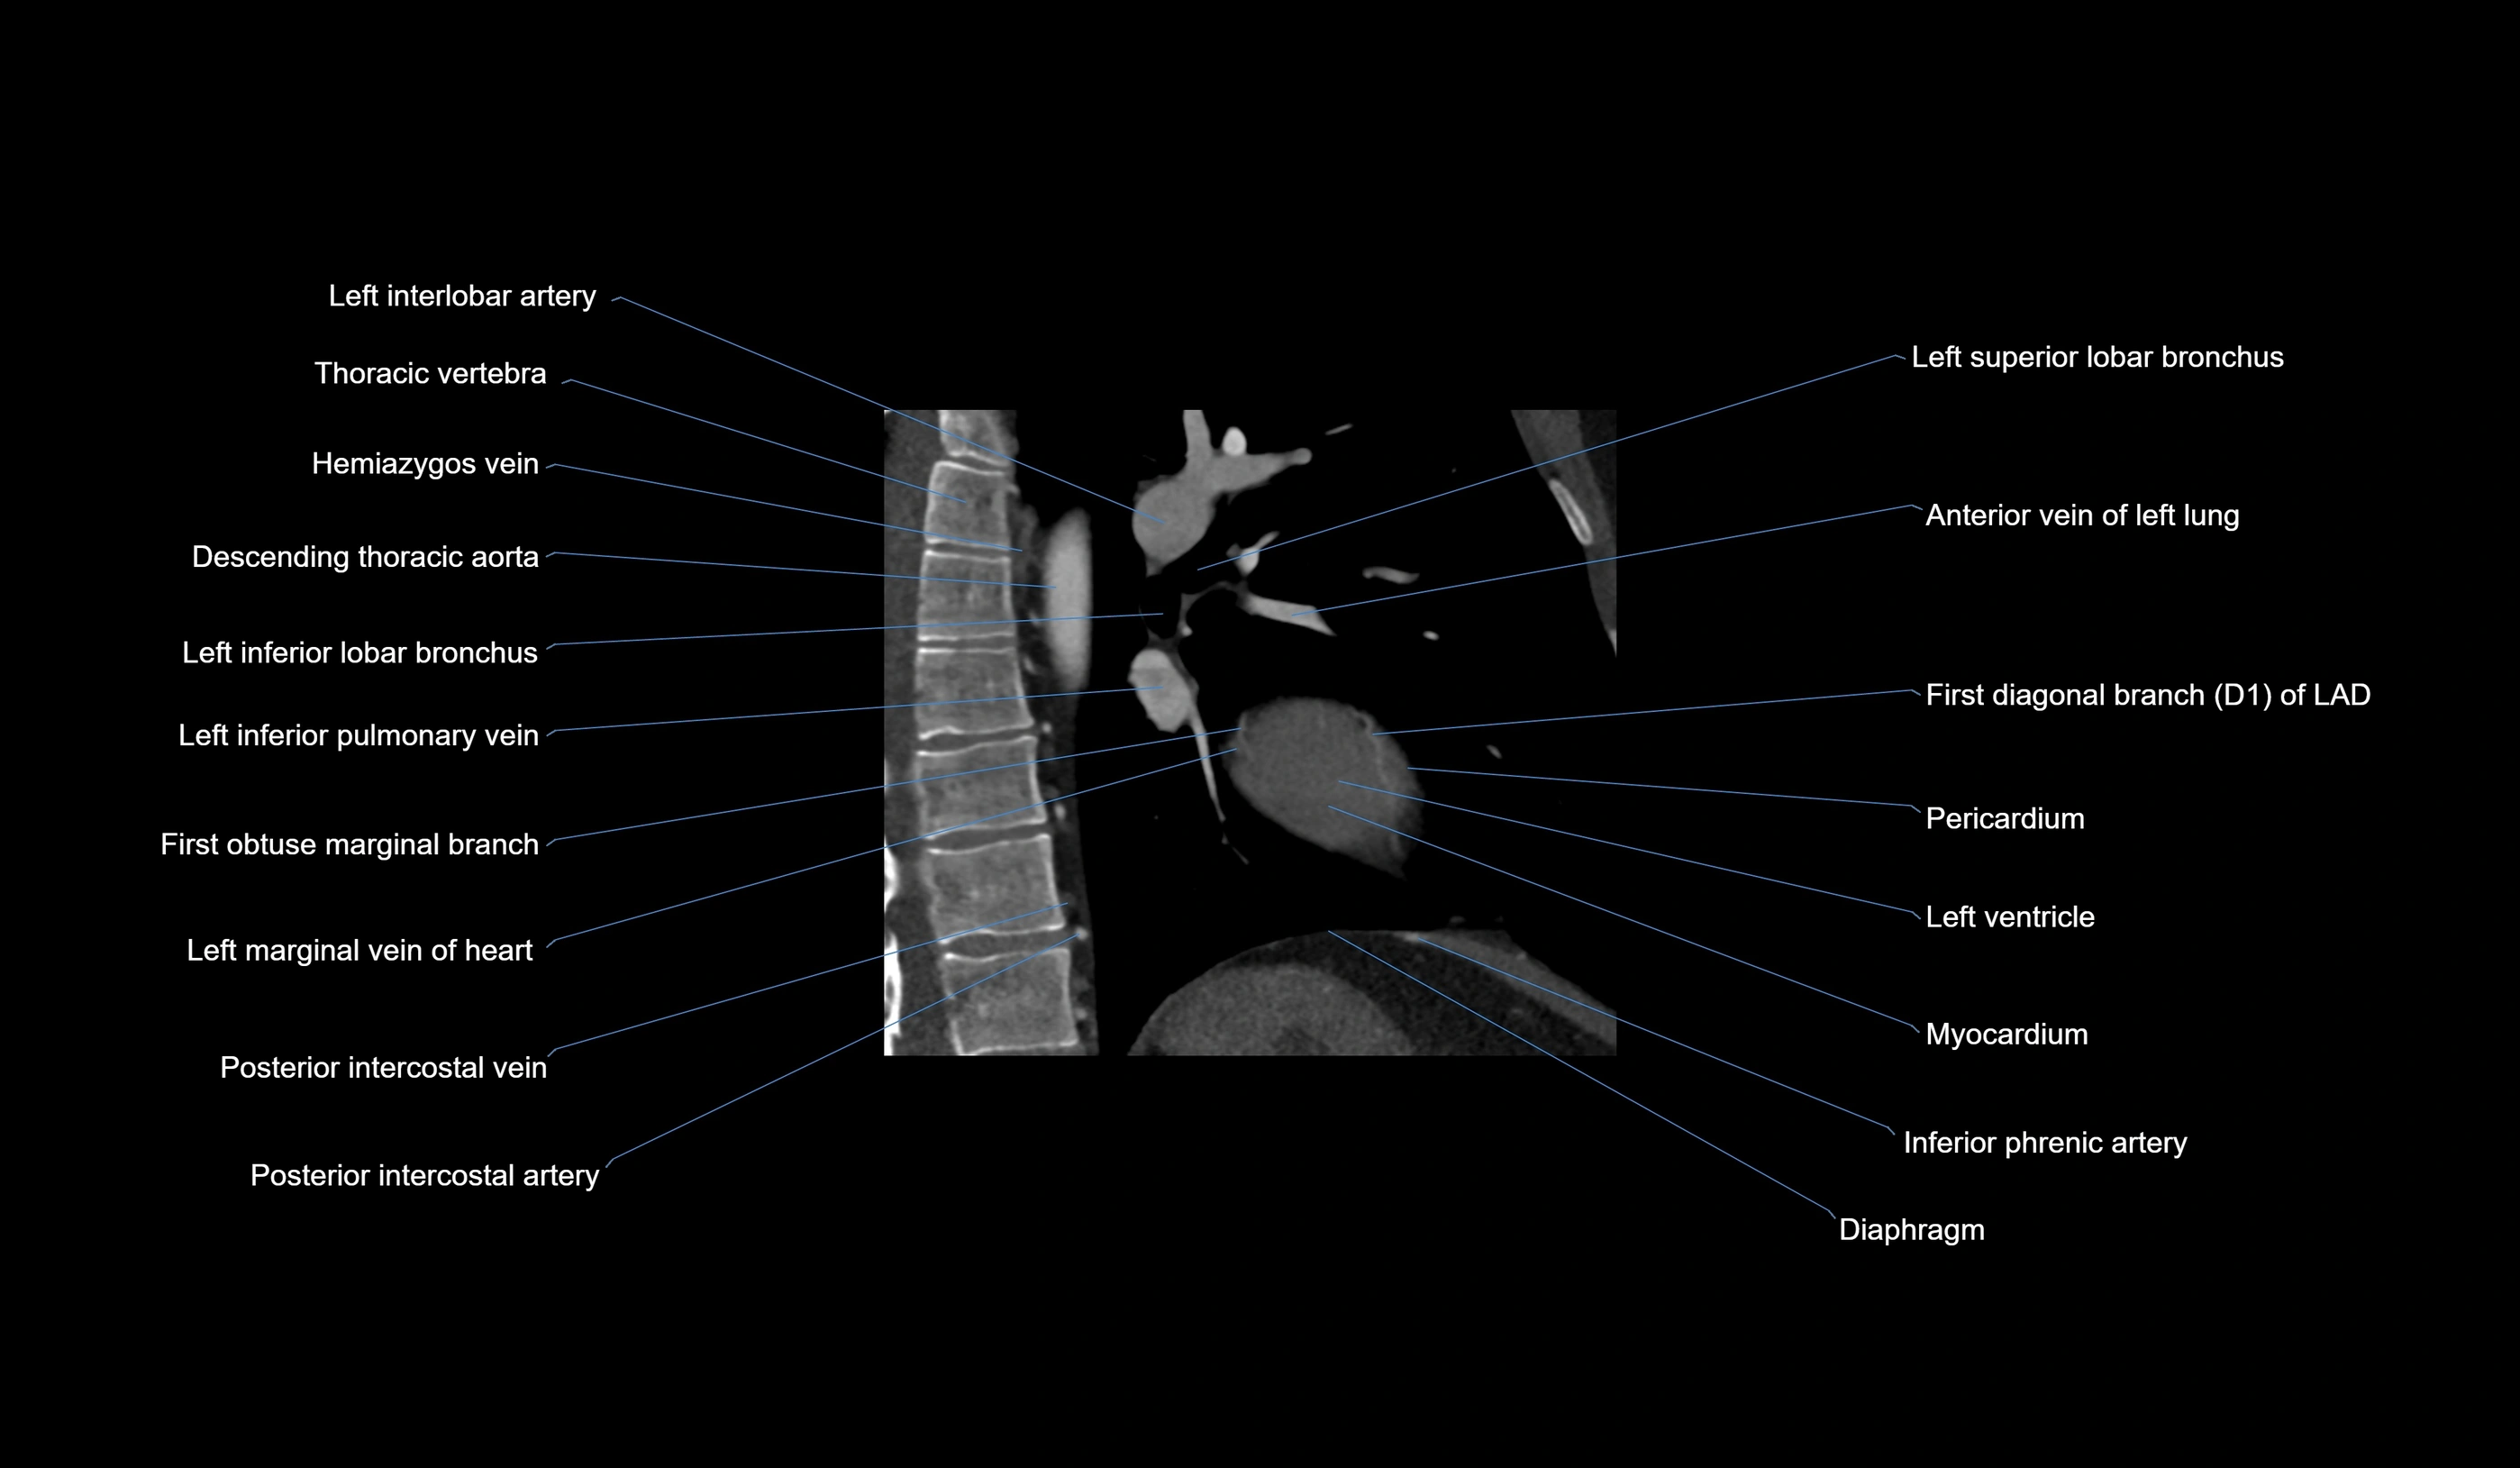

CT images